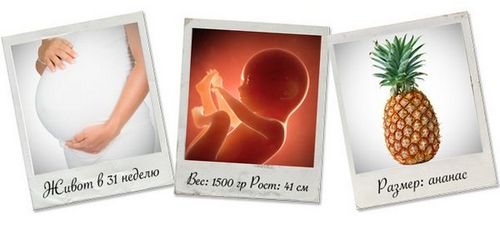

Ваш майбутній дитина на 31 тижні вагітності

Вітаємо з початком 31 акушерської тижні! Йде восьмий місяць вагітності.

Розміри плода на 30 тижні вагітності можна порівняти з розмірами ананаса. Його зріст від верхівки до пальчиків ніг складає 40 см, а вага наближається до 1400 гр. Починаючи з 31 тижня вагітності і до самих пологів плід буде набирати приблизно 225 гр в тиждень, хоча надбавка у вазі може дещо варіювати в одну або іншу сторону.

- Вік плоду: 29 тижнів

- Вага плоду: 1350 - 1680 гр.

- Зростання плоду: 37.5 - 41.5 см.